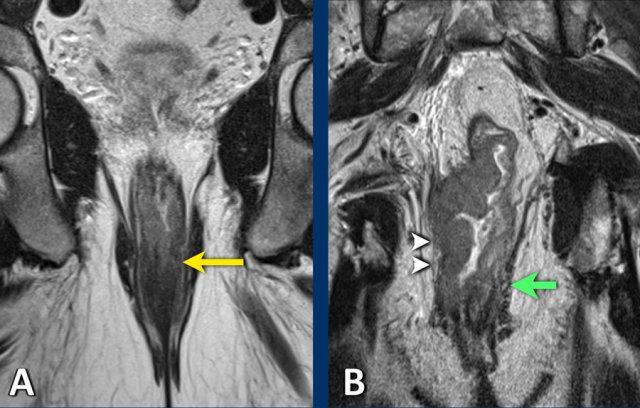

Hạch bạch huyết bên (chậu trong/bịt)

Các hạch bạch huyết chậu trong và bịt bên chủ yếu được đánh giá theo kích thước, với ≥7 mm (trục ngắn) là tiêu chí chính cho cN+.

Đặc điểm hình thái học—ranh giới không rõ ràng,

tín hiệu không đồng nhất, hình dạng tròn và mất rốn mỡ—có thể hỗ trợ

chẩn đoán ác tính trong các hạch kích thước trung bình (5–7 mm), đặc biệt nếu có nhiều hạch hoặc

khi có sự hiện diện của các hạch bên rõ ràng bệnh lý khác.

Yêu cầu Báo cáo

Bất kỳ hạch N+ bên nào (dù đã được gộp vào phân loại cN chung) đều phải được nêu bật riêng trong báo cáo MRI, với vị trí và kích thước được chỉ định cụ thể, vì những hạch này cần được điều trị có mục tiêu để ngăn ngừa tái phát bên.

Hình ảnh

- Hình ảnh bên trái: Hạch bạch huyết bệnh lý 9 mm ở khoang bịt bên trái (mũi tên), được xác định tại thời điểm phân loại giai đoạn ban đầu. Cần xạ trị và/hoặc cắt bỏ riêng biệt để tránh tái phát bên ngoài.

- Hình ảnh bên phải: Bệnh nhân được điều trị bằng phương pháp TME tiêu chuẩn (không cắt hạch bên) đã xuất hiện khối u không đều ở khoang bịt trái, phù hợp với tái phát hạch bên.